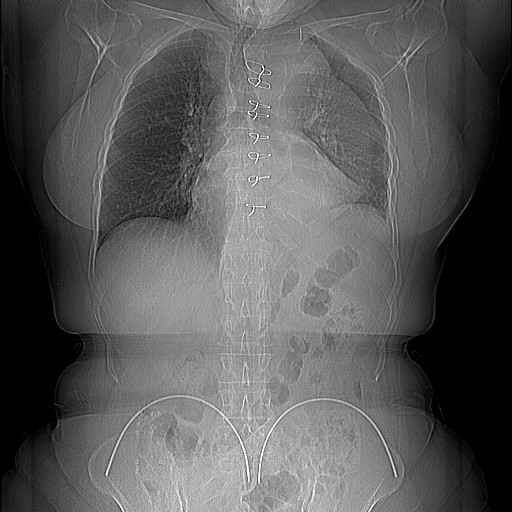

Доктор Жан Митрев заедно со својот тим успешно изведе сложена хибридна операција ФЕТ (Frozen Elephant trunk). Оваа операција претставува решение за комплексна состојба на распукување (дисекција) на аортата, при што се прави вградување на специјална аортна протеза на аркусот (лакот) и на десцедентната (спуштачкиот дел) на аортата.

Операцијата е изведена кај пациентката на возраст од 66 години во животозагрозувачка состојба со хронична компликација – аневризма што довела до колапс на левото белодробие и проблеми со дишењето. Ова не е прва операција за неа. Претходно кај пациентката била направена итна операција за замена на коренот на аортата заради акутна Стенфорд А (Де Бејки тип 1) дисекција, со цел санирање на тогашното распукување (дисекција) на аортата и спасување на животот на пациентката.

Оперативниот зафат иако во медицината се практикува подолго време, во континуитет се унапредува со нови техники. Но, заради комплексноста на целиот процес и вклучувањето на различни интервенции и пристапи, ретко се применува. Успешноста на зафатот покрај специјалноста и комбинирањето на интервенции, во голема мера зависи и од употребата на најнови модели протези и примена на соодветни стратегии за заштита на миокардот, како и церебрална и висцерална заштита.

Наречен е хибриден зафат затоа што комбинира ендоваскуларен третман со класична операција со употреба на хибридна протеза и интердисциплинарен тим во состав: кардиохирург, интервентен радиолог, анестезиолог, перфузионист, инструментарка.